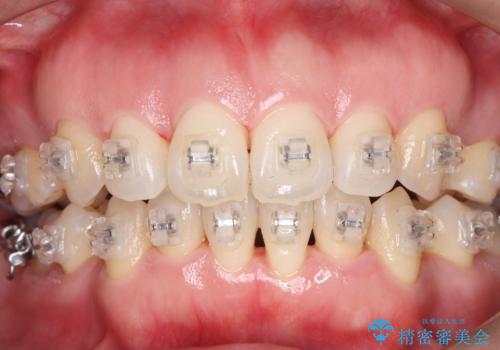

- ワイヤー矯正中の患者様です。

装置の周りの着色が気になるとのことで、エアフローを行いました。。

「着色が取れて、笑うのが楽しみになりました!」

歯面が滑らかになり、清潔感がアップ。

エアフローは定期的に行うことで、より健康的な口腔内を保つことができます。